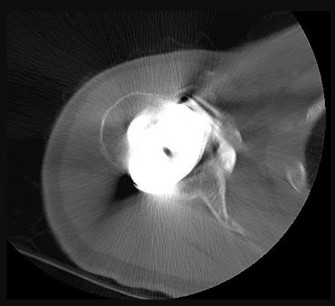

CLINICAL SITUATION FOR QUESTIONS 28 THROUGH 31

Figure 28 is the radiograph of a 78-year-old patient with a painful uncemented hemiarthroplasty of 6 months duration. Complete blood count and erythrocyte sedimentation rate findings are negative, and trauma is not a factor.

QUESTION 25

of 100

The radiograph shows components that are

1

subluxed.

2

fractured.

3

loose and potentially infected.

4

normal.

- loose and potentially infected._

.

QUESTION 26

The next step in this patient’s workup should be

aspiration.

observation.

physical therapy.

revision to total shoulder arthroplasty.

- aspiration.

QUESTION 27

If aspiration findings are negative or equivocal, the diagnosis can be established with

arthroscopy.

a bone scan.

a serum white blood cell level.

a C-reactive protein level.

- arthroscopy._

QUESTION 28

If the culture results are positive, which treatment will most likely resolve the infection?

Arthroscopic debridement

Intravenous antibiotics

Single-stage revision

Double-stage revision

Osteolysis of this magnitude is uncommon in the setting of an uncemented hemiarthroplasty. Further workup for infection is indicated, such as aspiration under fluoroscopy or ultrasound. Infection needs to be ruled out before proceeding. Observation and physical therapy are not indicated. Arthroscopy has been shown in several studies to have greater sensitivity and specificity than aspiration and can be especially effective to obtain cultures of slow-growing organisms such as Propionibacterium acnes. Blood tests are unreliable, and a bone scan would not reliably differentiate between loosening and infection. Arthroscopic debridement would not be reliable for treatment. Intravenous antibiotics can be used for suppression, but the best results in terms of resolving the infection would be achieved with 2-stage revision.